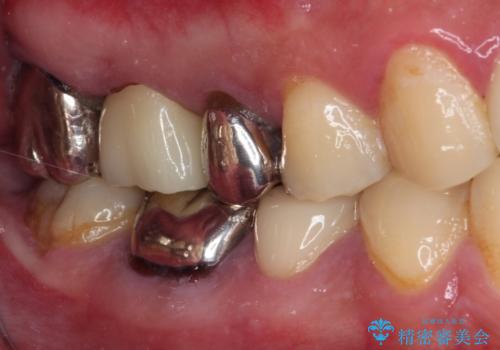

- ものが挟まるとのことで来院された患者様です。

一度は治療せずに放置していましたが、1年後のメインテナンスの際に悪化していることが分かったことから、補綴治療を行うこととしました。

神経を抜いてある歯はむし歯が進行しても痛みを感じることがないため、気がついたときには著しくむし歯が進行している可能性があります。

早めの対応とすることで、抜歯を回避できることはもちろん、外科処置などの本来必要のない処置を行わずに対処することができました。